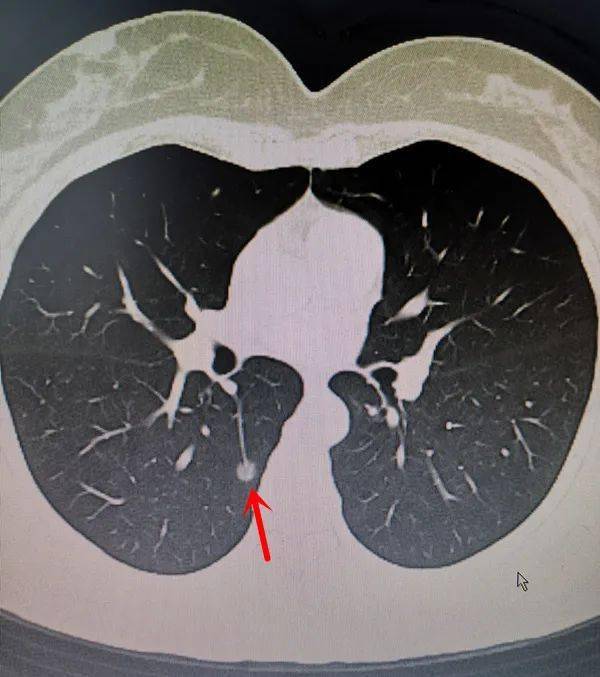

5mm的微小实性结节竟是恶性程度最高的肺癌

图片尺寸640x437